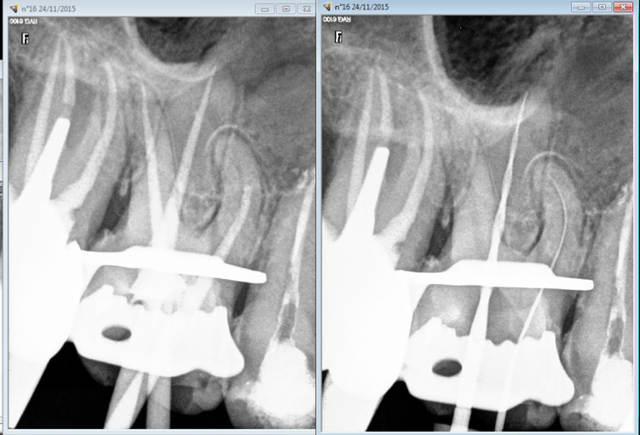

Capture d e cran 2015 11 24 23.14 - Eugenol

J'ai ensuite retrouvé mon calme sur la suivante. -))))

Capture d e cran 2015 11 24 23.26 - Eugenol

Tu dis rien en général, il ne se passe rien. C'est un aléa thérapeutique. Tu surveilles l'évolution éventuelle. Un apex en crochet par exemple ca arrive et à tout le monde endos exclusifs inclus ( moins peut etre parce qu'ils prennent leur temps et qu'ils font ca toute la journée)

Je paye une caisse de champagne à l'endo exclusif qui va me retirer ca par voie orthograde.-)))

Ca c'est à cause du localisateur d'apex, j'y étais mais ce con me disait que j'y étais pas tu insistes et paf. ( il a merdé sur l'autre canal d'ailleurs dépassement de 2 mm cone radio coupé de 2mm)

Capture d e cran 2015 11 25 13.18 - Eugenol

Et non 2 canaux et pas facile de progresser jusqu'à l'apex. Et doublement pas facile le sujet étant stressé à fond ( genre je réagis au moindre bruit et vibration en l'absence de toute douleur obligé en plus de travailler à sec car panique avec le spray).

Capture d e cran 2015 11 25 17.58 - Eugenol